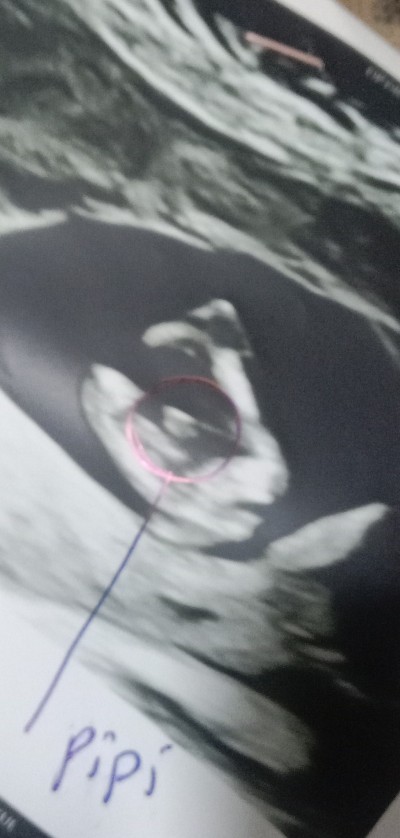

Banada 12 hafta 6 günlük  kesin emininim cinsiyeti belli soylleyimmi dedi yüzde kaç hocam dedim yüzde yüz erkek dedi de çevremdekiler yanilabilir diyince şüpheye düştüm

Bizim bu seki bacak arasi